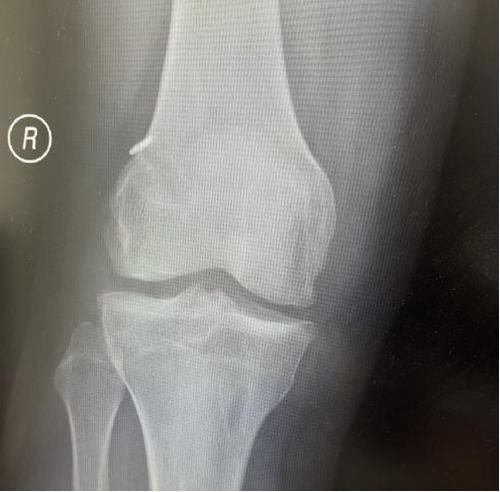

膝關節韌帶損傷磁共振

我院骨科三病區近期收治了4名膝關節交叉韌帶損傷患者。25歲的齊先生,因打籃球時不慎扭傷左膝,致右膝腫痛,遂來我院治療;30歲趙先生酷愛足球,扭傷右膝關節來我院就診;50歲的張先生、42歲劉先生因騎車滑倒摔傷、膝關節腫痛不適、活動受限,收治入院。骨科三病區李鵬主任團隊詳細查體以及完善影像學檢查后進行診斷:幾位患者共同診斷均有“前交叉韌帶損傷”,不同程度合并有“半月板損傷”、“股骨軟骨損傷”、“內側副韌帶斷裂”。